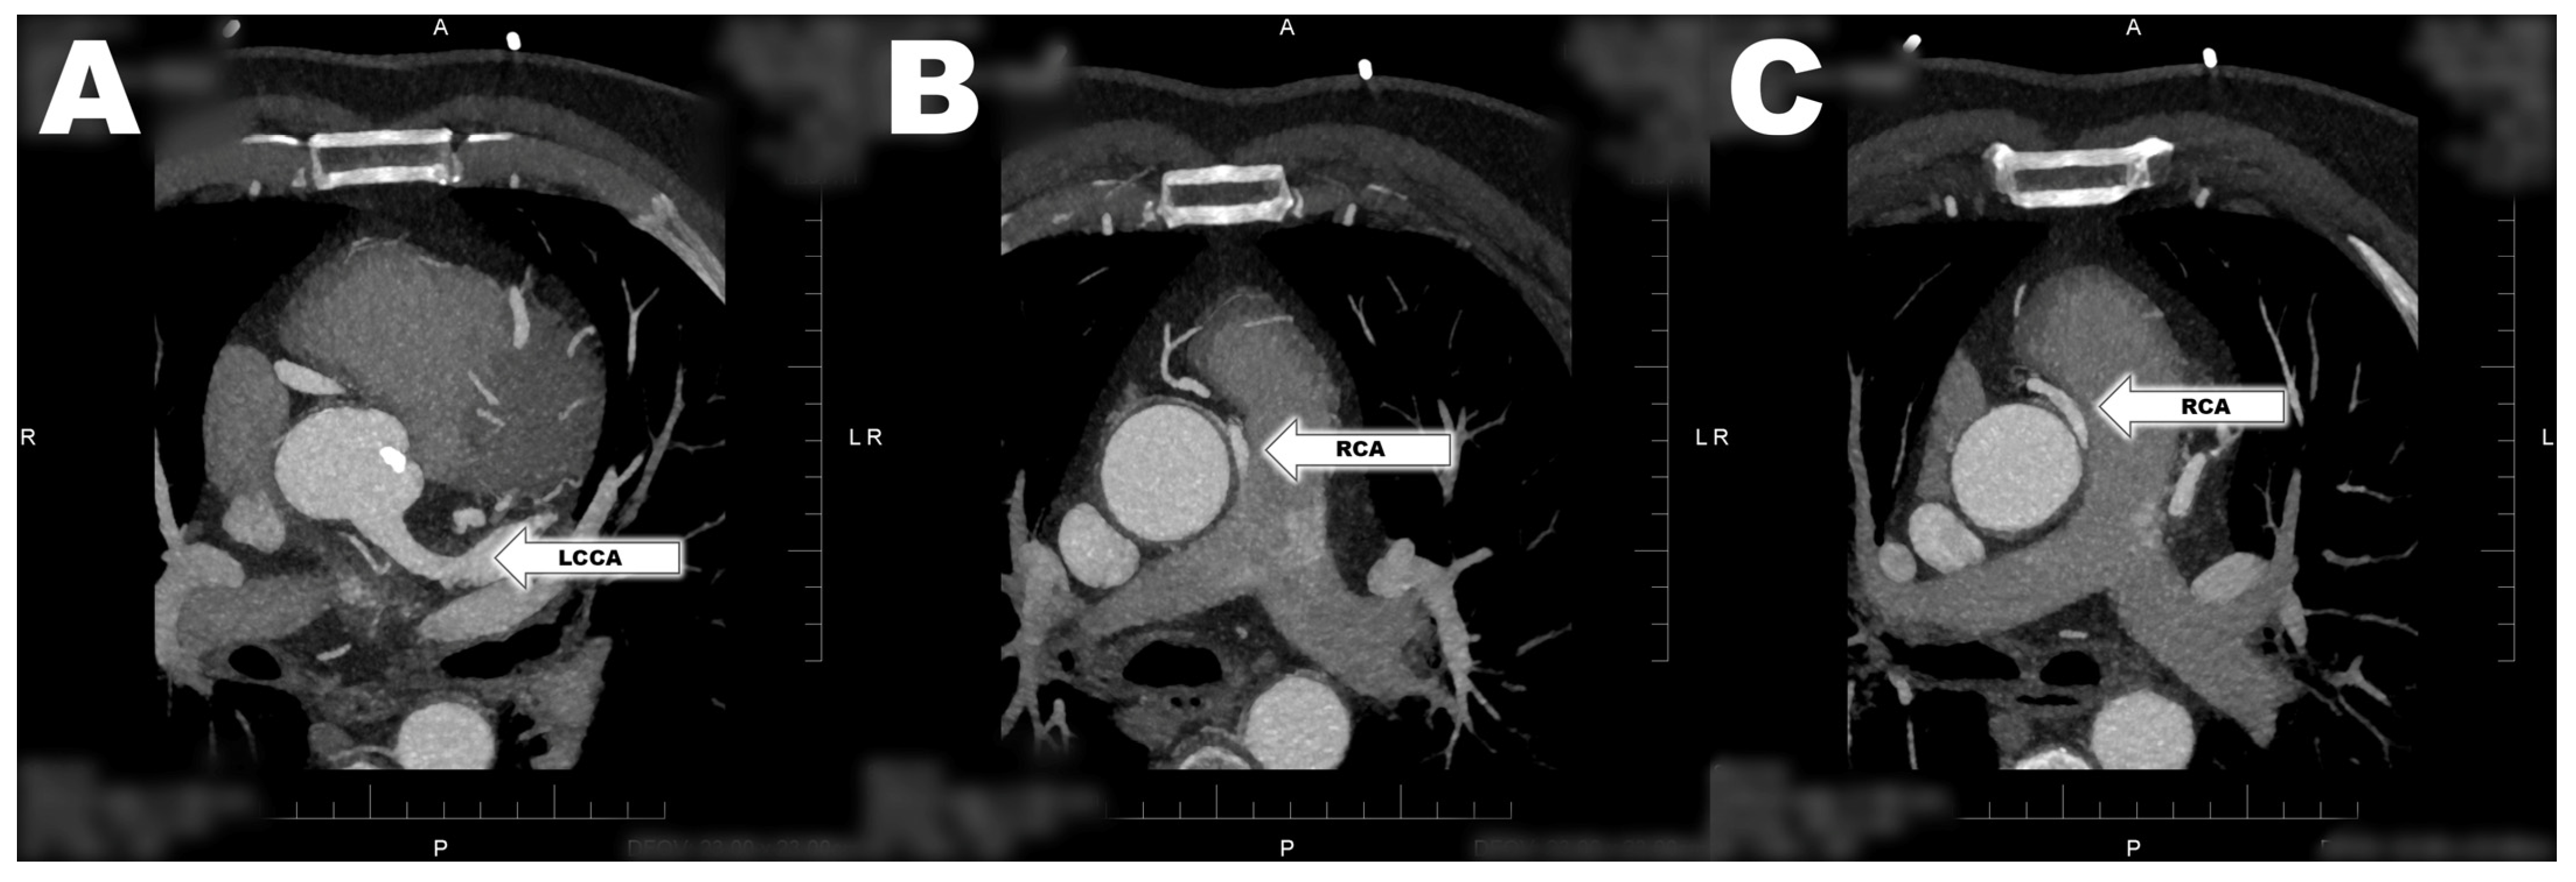

Anomalous Arising of Right Coronary Artery from the Pulmonary Artery

2. Case Report